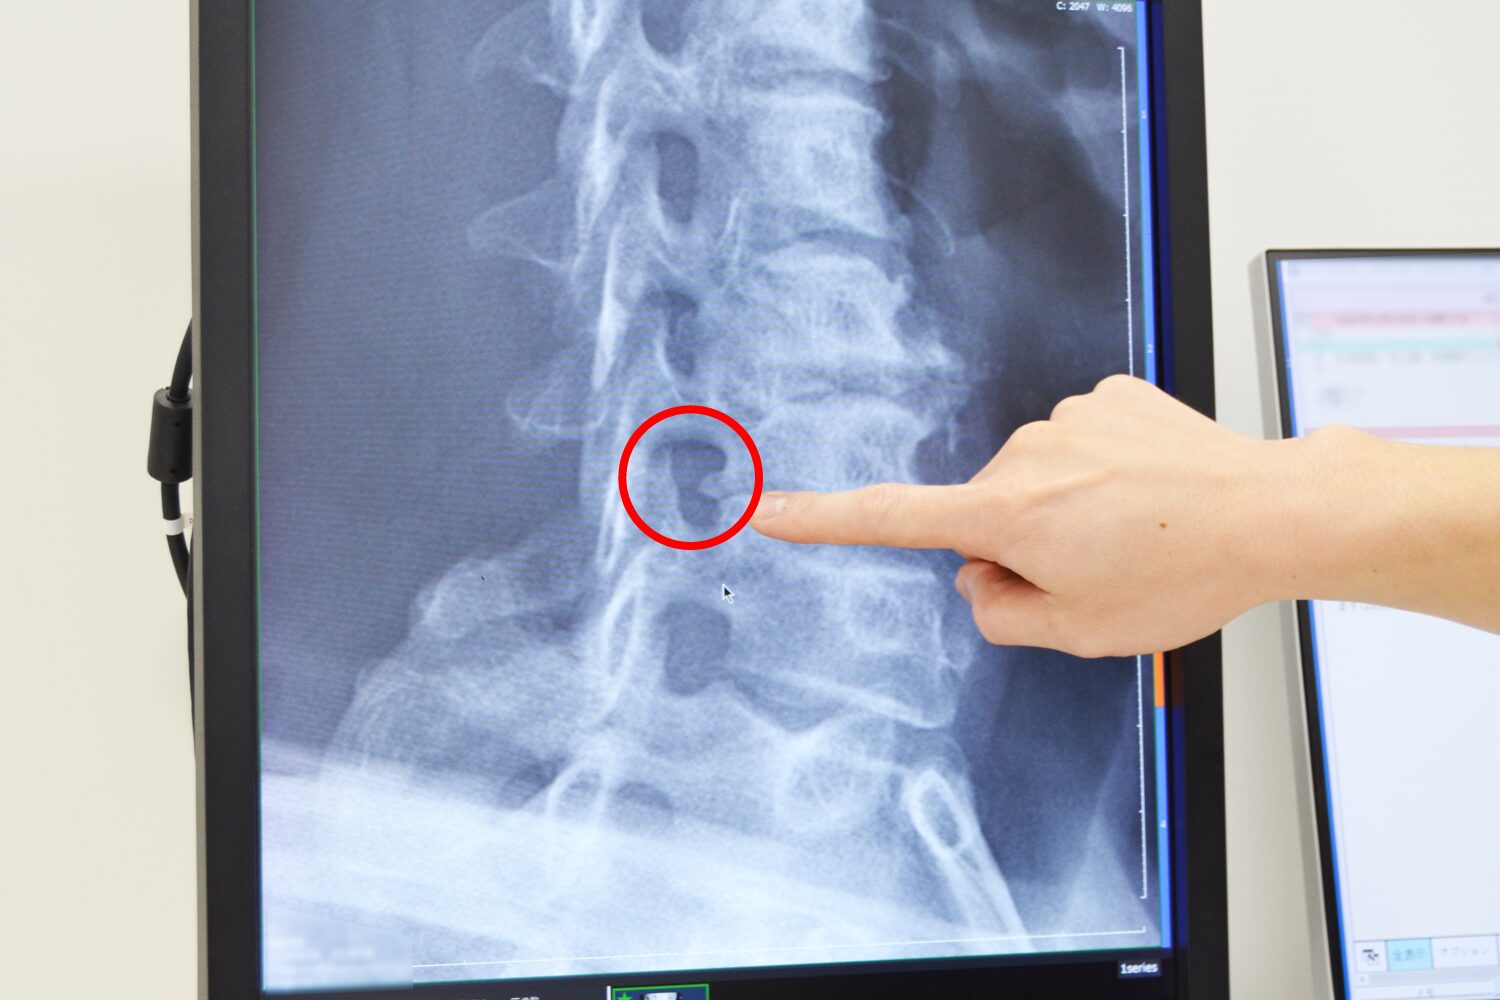

頚椎症のレントゲン画像

こちらが頚椎症の実際のレントゲン画像なのですが、骨の形状が変化して出っぱっているのが確認できます。このように骨がぴょこんと出てくると、首の骨の後ろに通っている神経に骨が触ってしまって腕や手がびりびりしてしまうことがあります。

こちらは斜めから見ている画像ですが、他の部分に比べて黒い部分の形が異なり、骨の先端がぴょこんと出ているのがわかります。普通の正常な状態では、このような出っ張りはありません。